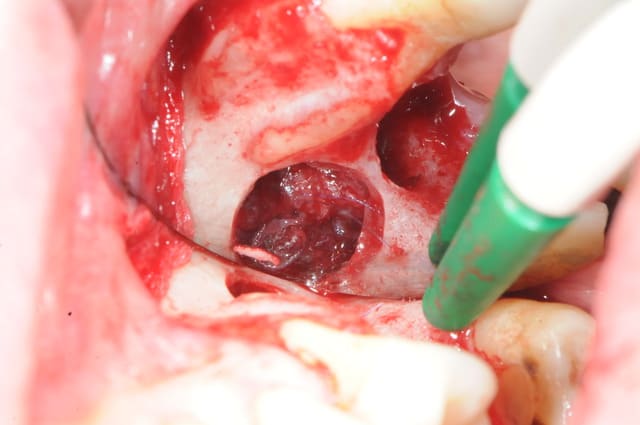

photo 1:

je cherche, je cherche, je soulève la membrane, et ..ohh! surprise!?

le dodo lé pas là !

mais ou est il ?

merde! ce con d'implant est parti faire un tout de poney sur sa selle turcique ou quoi ?? il est aller boire un coup avec les amygdales ?

bon, ben, si c'est pas resté sous le sinus, c'est que c'est dedans!

pas de pus, ni d'écoulement purulent pendant le soulèvement. comme il faut bien le trouver, je cherche sans ménager la membrane et ce qui devait se passer arriva; déchirure de la membrane.

pour une fois c'était presque voulu.

une fois percée, j'ai littéralement vidé le sinus du pus qu'il contenait avec l'aspiration.

désolé, pas de photos! vous comprendrez que c'est pas toujours facile de les faire en cours d'intervention.

2: comme il me fallait insérer la canule d'aspiration à travers l'opercule de la membrane pour vider le contenu sinusien, et comme l'aspiration venait me faire ch... à aspirer la membrane, j'ai décidé de la suturer sur le petit pont osseux pour la rendre plus stable.

3:

après de longues recherches et avec de la chance je l'ai enfin sorti. toutes la salle s'est écriée " ça y est le voilà!"

j'ai alors dit au patient; " félicitation, c'est un garçon!"